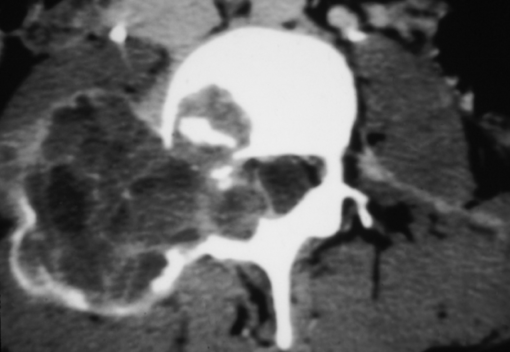

- Synovial Cyst

- Synovial Cyst Posteriorly Projecting